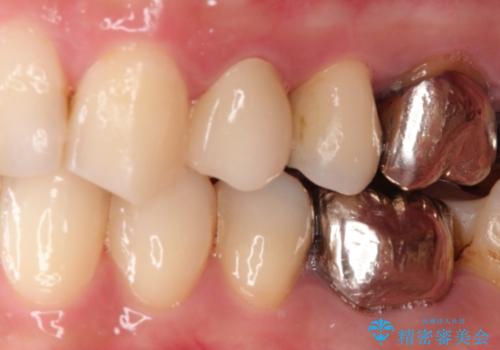

大きい虫歯 根管治療〜オールセラミッククラウン

- 大きな虫歯を認めた患者様です。

自発痛を認めたことから、不可逆性歯髄炎の診断を行い治療を介入しております。